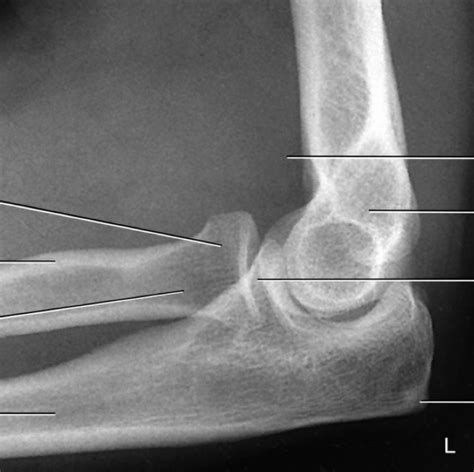

Next up is the Lateral view , which provides a side-on perspective of the elbow joint. For this view, the elbow is typically flexed at 90 degrees with the thumb pointing upwards. This position allows for optimal visualization of the olecranon process, radial head, and the relationship between the humerus, radius, and ulna. The lateral view is essential for evaluating the olecranon for fractures, assessing the anterior humeral line, and identifying joint effusions.

The anterior humeral line is a crucial reference point in the lateral view, especially in pediatric cases. This line is drawn along the anterior aspect of the humerus and should intersect the middle third of the capitellum. If the capitellum lies anterior to this line, it may indicate a supracondylar fracture with posterior displacement. Additionally, the lateral view is excellent for detecting joint effusions, which appear as a dark area (increased lucency) anterior to the distal humerus, often referred to as the anterior fat pad sign or sail sign .